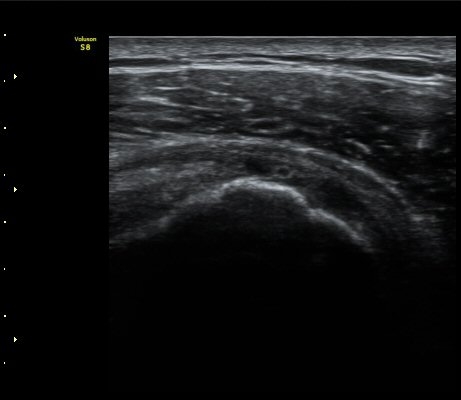

±Ø»ó°Ç ¿ÜÃø Á¾´Ü¸é°Ë»ç ½Ã Á¡¾×³¶ ºÎÁ¾ÀÌ °üÂûµÊ(±×¸² 4).